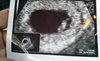

Ja mam umówioną wizytę w Luxmed w piątek wtedy też wezmę L4 i badania pewnie dostane ale dzisiaj nie wytrzymałam i umówiłam się prywatnie bo taki niedowiarek jestem :) a tu taki Robaczek już jest i serduszko słychać. Terminy z OM i USG się pokrywają 6+4 dni. Łezka poleciała.

Ale super, że jest serduszko [emoji3059] cudowne zdjęcie [emoji7]